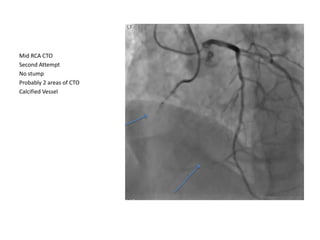

Mid RCA CTO

Second Attempt calcified vessel No stump

Probably 2 areas of CTO (mid and distal)

Second Attempt

No stump

Probably 2 areas of CTO

Calcified Vessel